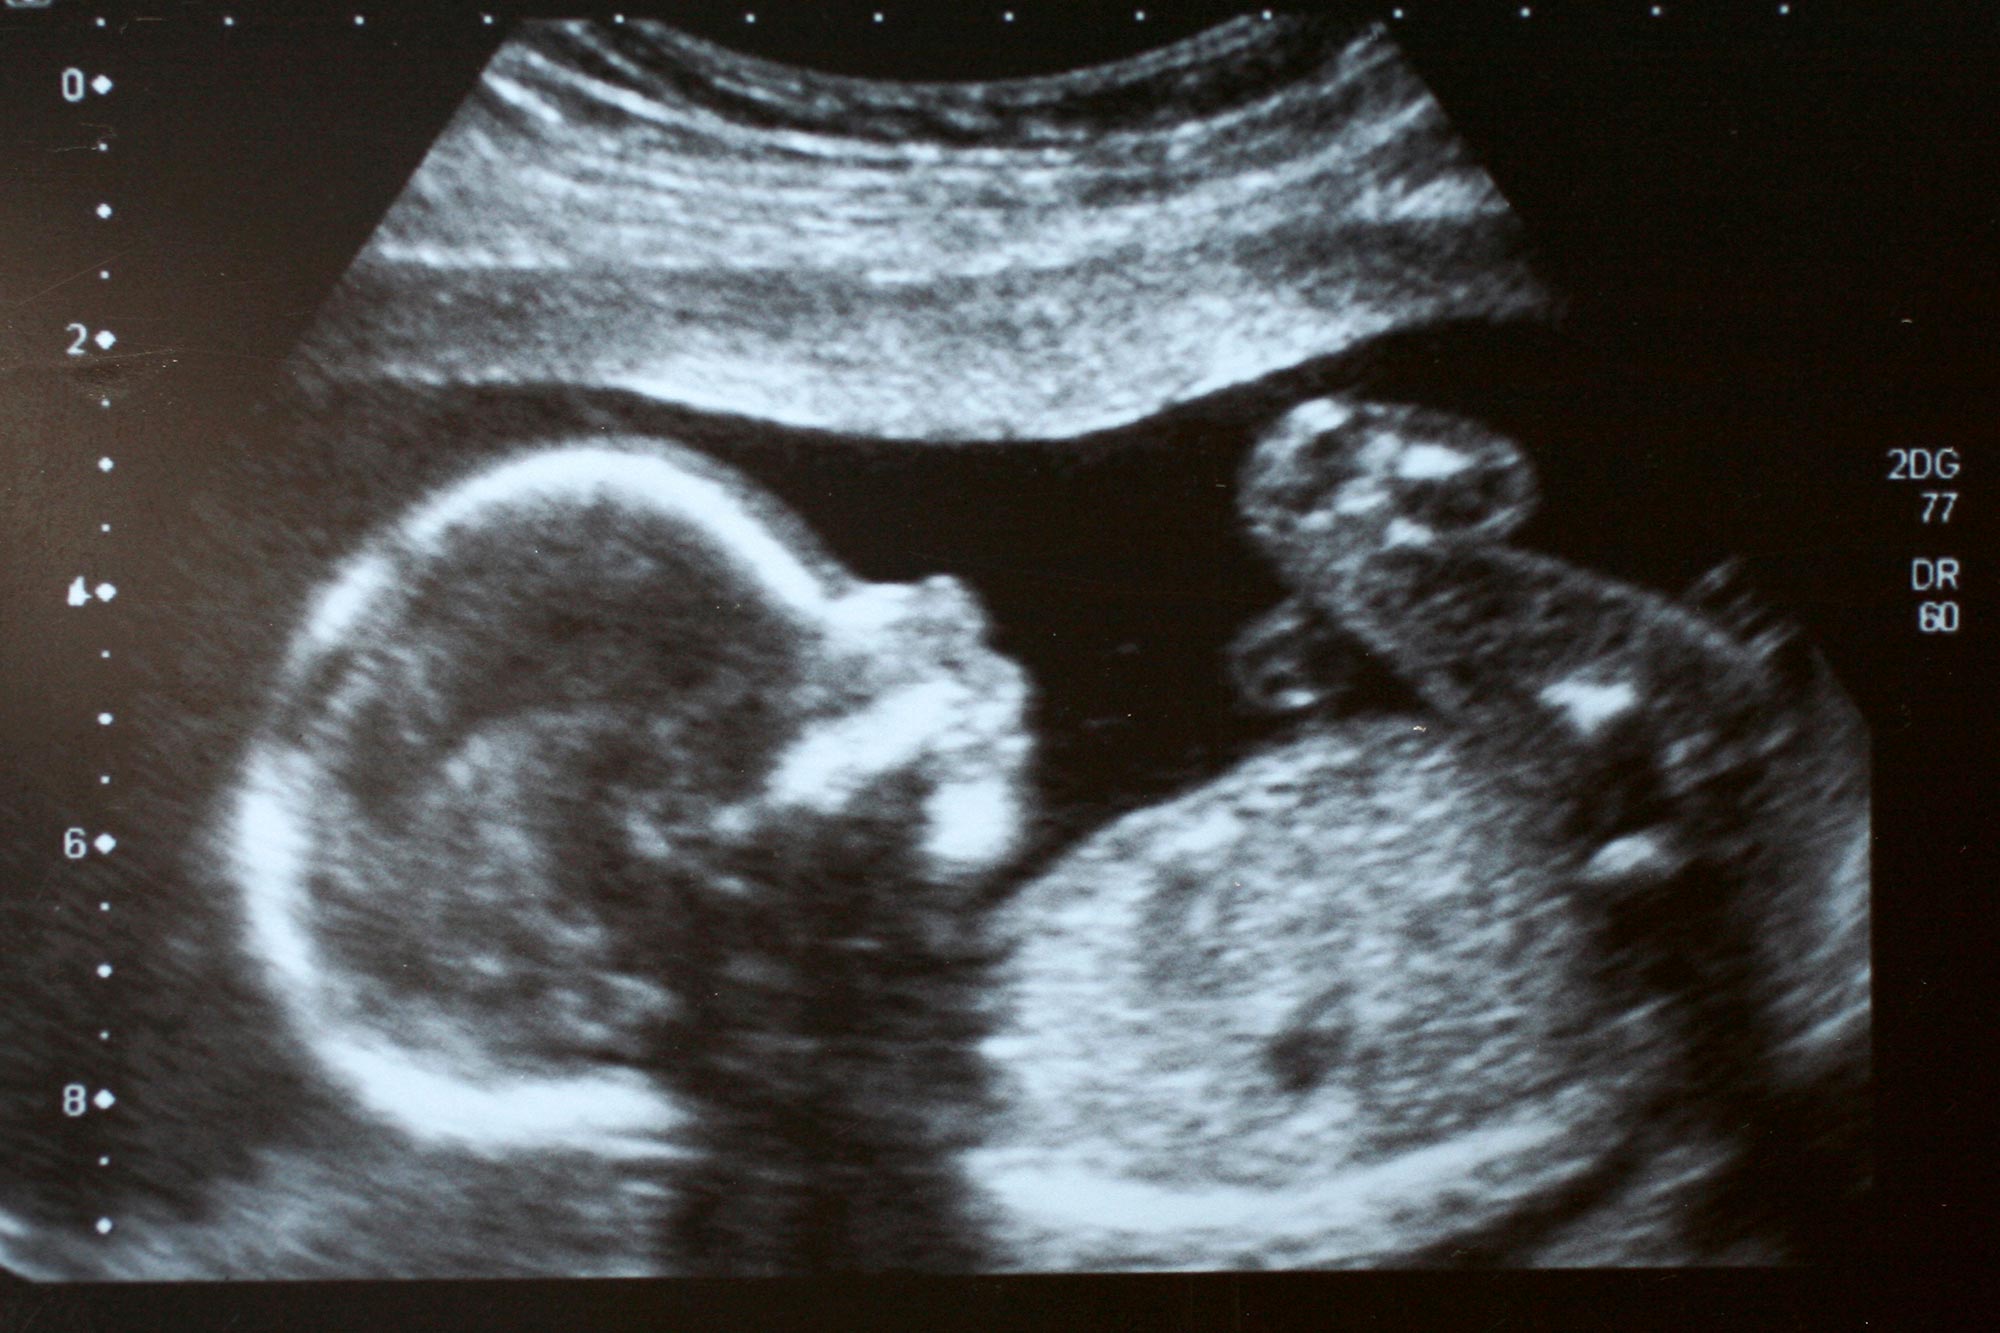

Pero los recientes cambios evolutivos no se limitan a la forma de la cara. En un estudio publicado en el último número de la revista Journal of Anatomy, se muestra que en poco más de un siglo se ha triplicado la incidencia de la llamada arteria mediana, una arteria ocasional del antebrazo, que se forma en el útero y generalmente desaparece durante el período de gestación.